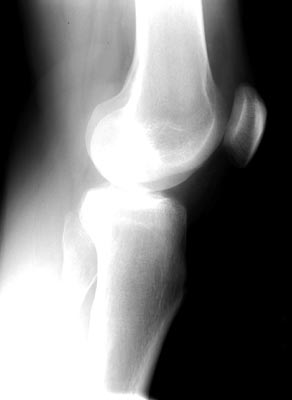

Lateral view